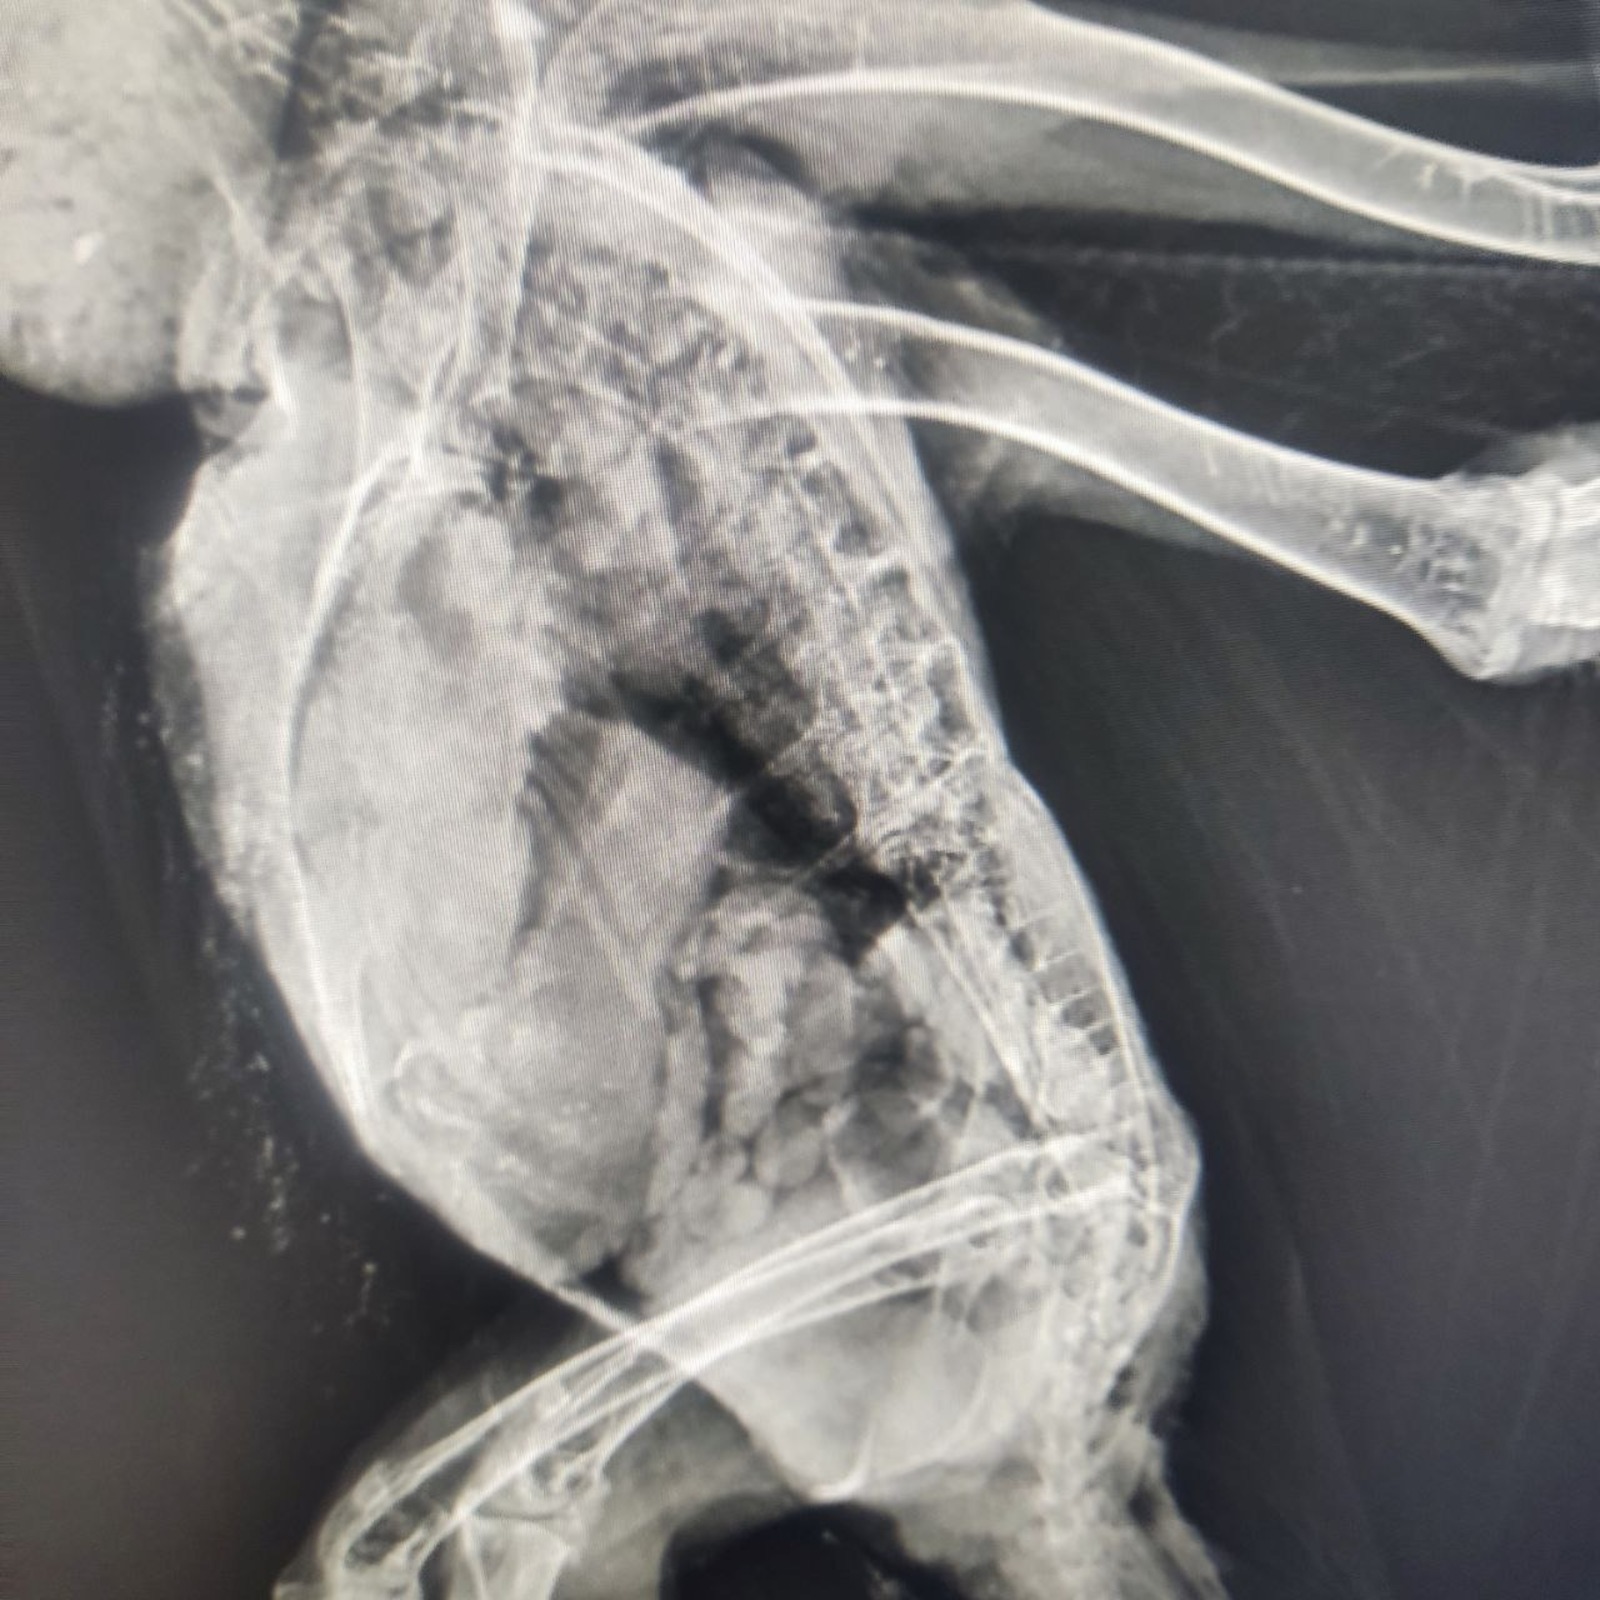

Обследование показало, что у хищника перелом позвоночника. Шансы на восстановление маленькие, но есть, сказал Дмитрий Стрельников.